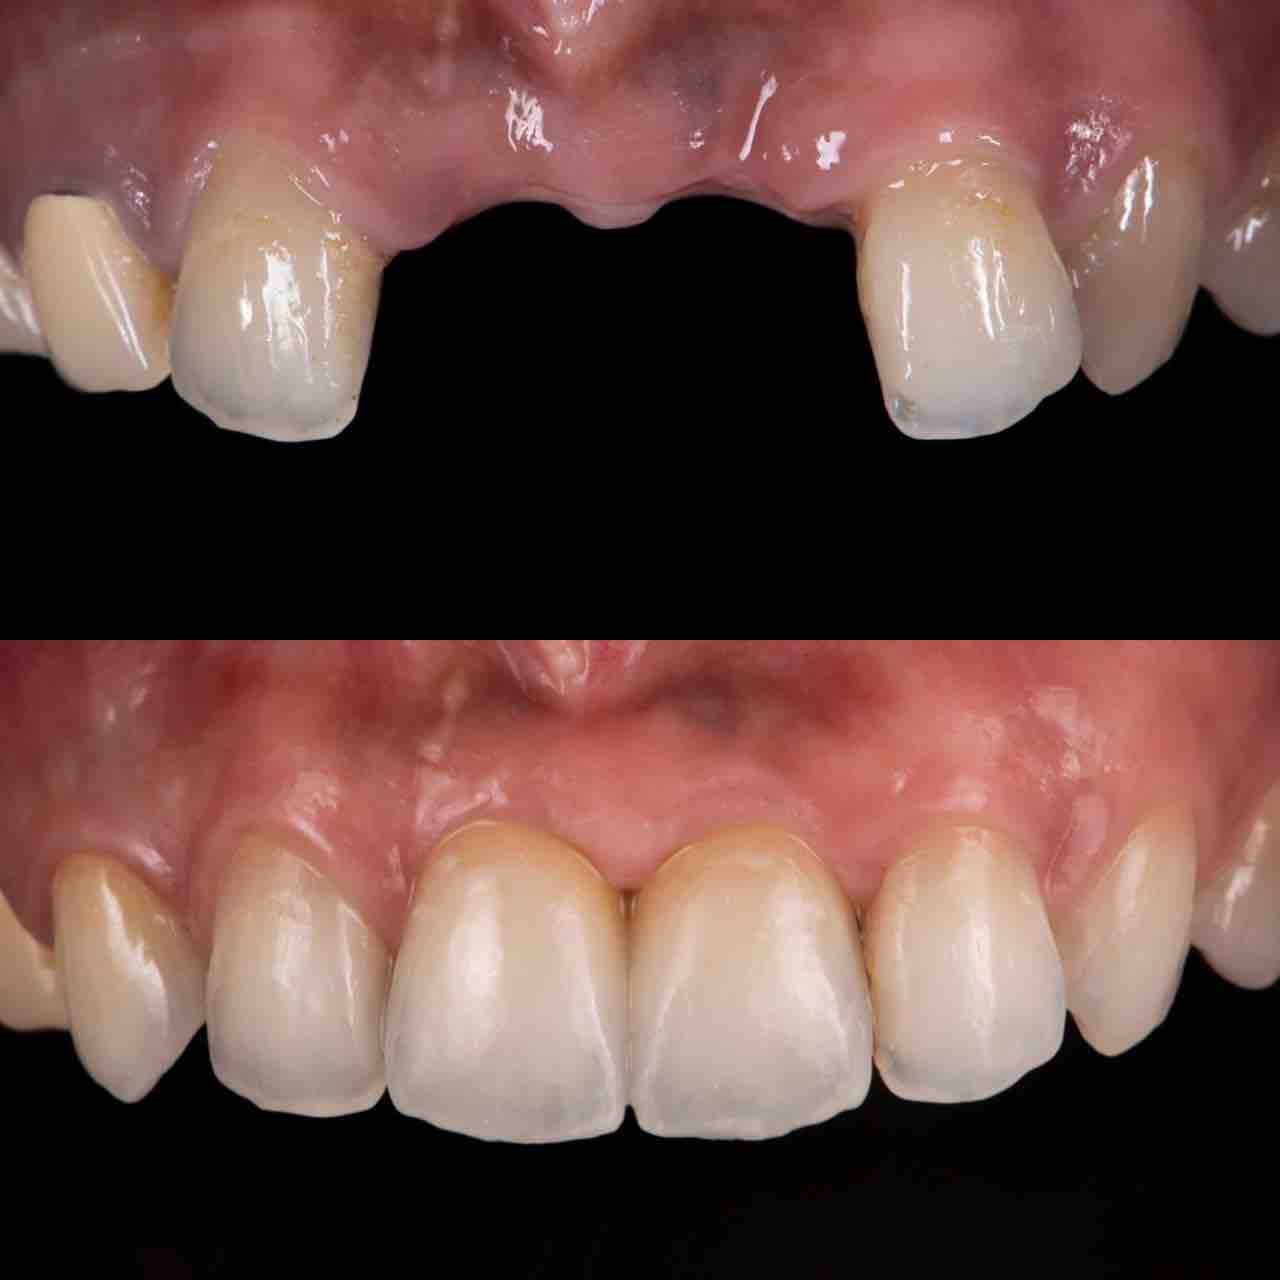

¥¤¥ó¥¹¥¿¥°¥é¥à¤ËºÜ¤»¤Æ¤¤¤ëÅö±¡¤Î¾ÉÎã¤Ç¤¹